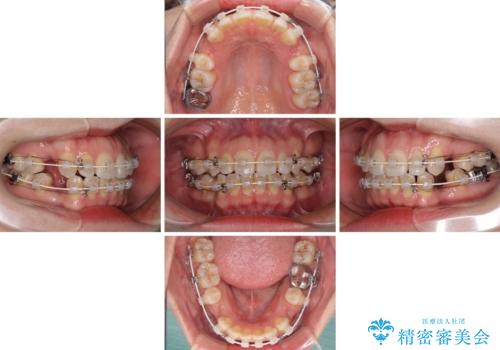

- 矯正装置

- 審美装置

- 治療計画

- 唇の閉じにくさを気にして来院された患者様です。

上下左右第一小臼歯4本を抜歯し、ワイヤー装置にて口元を引っ込めるよう矯正治療を行うこととしました。